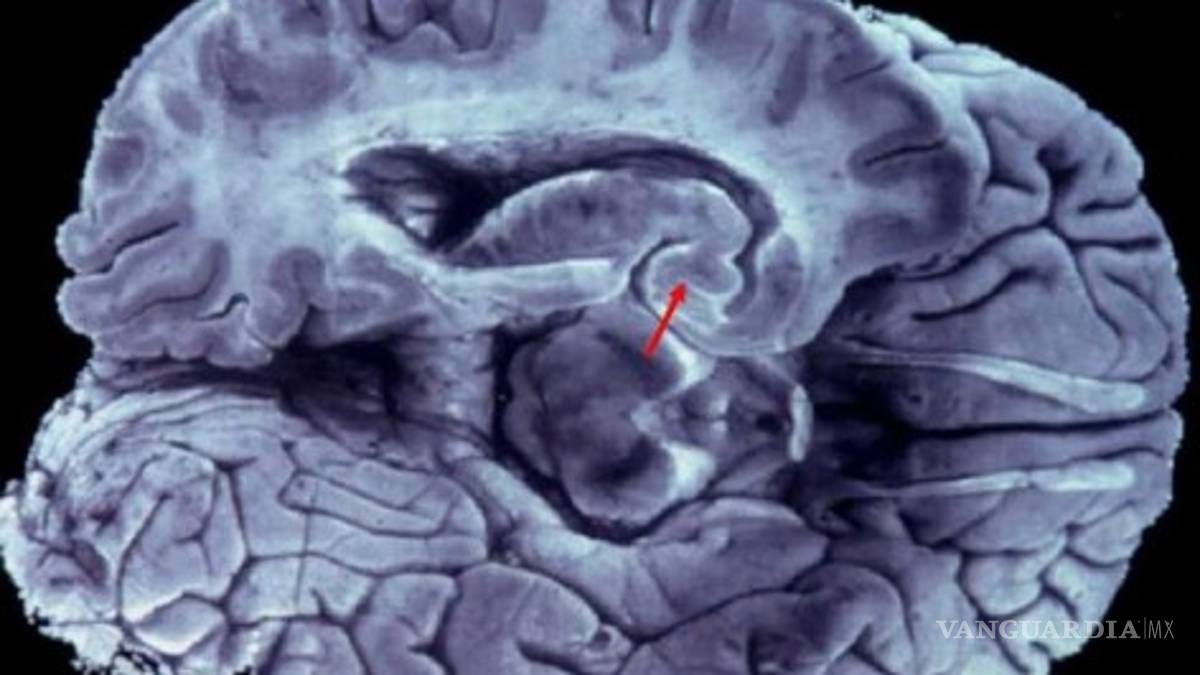

Con el apoyo de las nuevas herramientas, como la resonancia magnética, por ejemplo, es posible medir el volumen de las áreas cerebrales, en particular las involucradas con la memoria y compararlas con las de personas sanas.